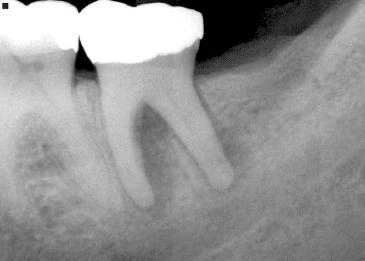

Hình 16. Khi có khoảng trống giữa chất trám bít ống tuỷ và thành ống tuỷ thì nghi ngờ cao có chia chân răng.